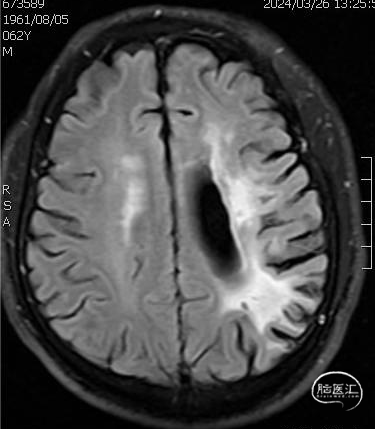

➢ 头颅MRI

左侧顶枕叶陈旧性梗塞,未见新发梗塞病灶。

➢ 头颅高分辨磁共振

管壁高分辨磁共振提示闭塞段斑块有强化,闭塞段不长。